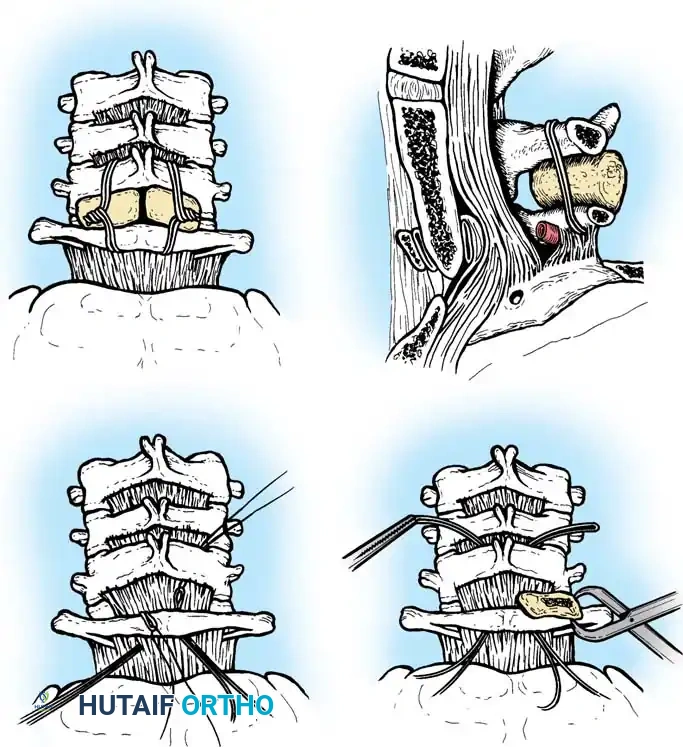

Posterior Cervical Fusion (PCF) and Instrumentation

Indications: Posterior tension band failure, irreducible facet dislocations requiring open reduction, or multi-level instability.

Surgical Steps:

1. Open Reduction: If a facet is dislocated, carefully lever the inferior articular process of the superior vertebra over the superior articular process of the inferior vertebra using a Penfield elevator.

2. Lateral Mass Screw Fixation:

* Utilize the Magerl or Roy-Camille trajectory.

* Magerl Technique: The entry point is 1 mm medial and 1 mm superior to the center of the lateral mass. The drill is angled 25 degrees laterally (to avoid the vertebral artery) and 15 degrees cephalad (to avoid the exiting nerve root).

3. Rod Contouring: Contour titanium or cobalt-chrome rods to match the patient's natural cervical lordosis and secure them to the screw heads with set screws.

4. Decortication and Fusion: Aggressively decorticate the lateral masses and facet joints with a high-speed burr. Pack the gutters with cancellous autograft (often harvested from the iliac crest) or high-quality allograft.

Fig 7. Posterior cervical lateral mass screw and rod construct, providing excellent biomechanical stability for posterior tension band failures.